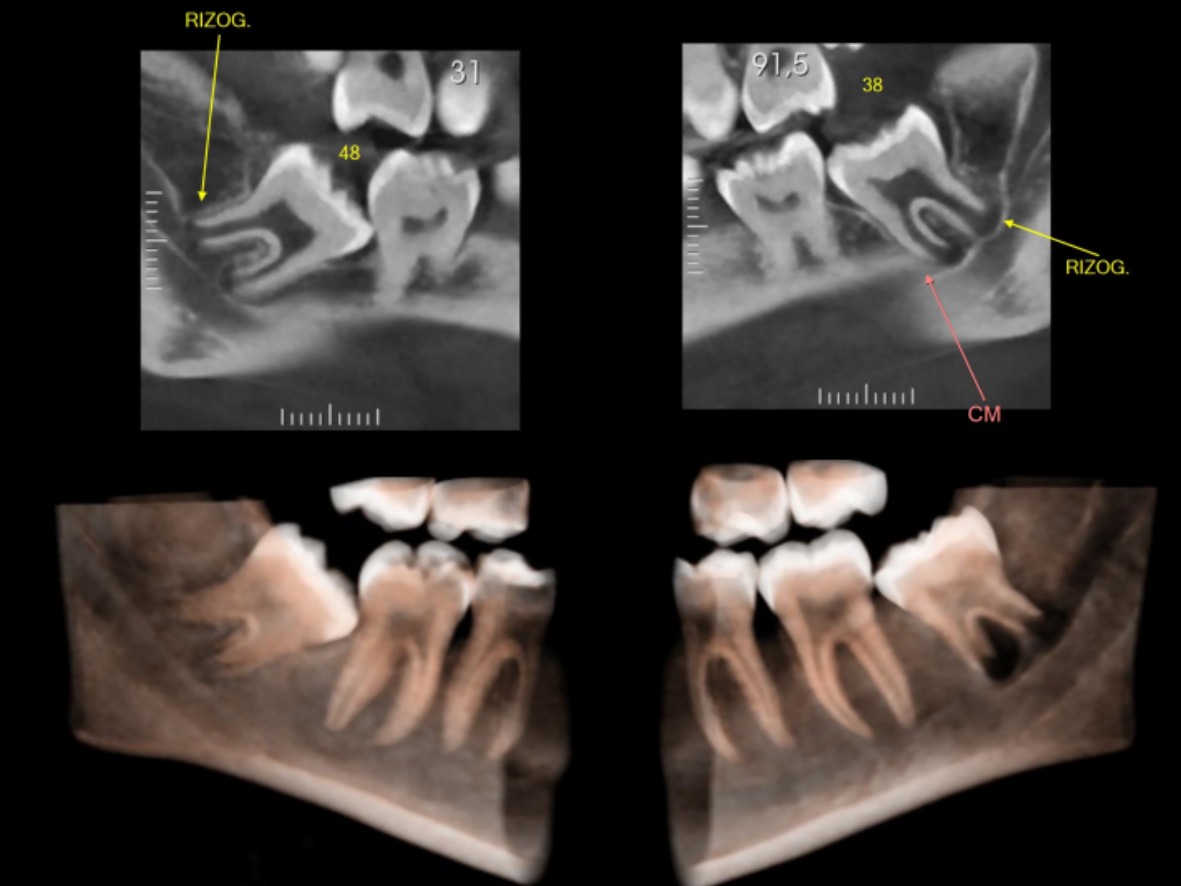

Tomografia Computadorizada

Exame 3D de alta precisão. Mostra detalhes de ossos, dentes e articulações.